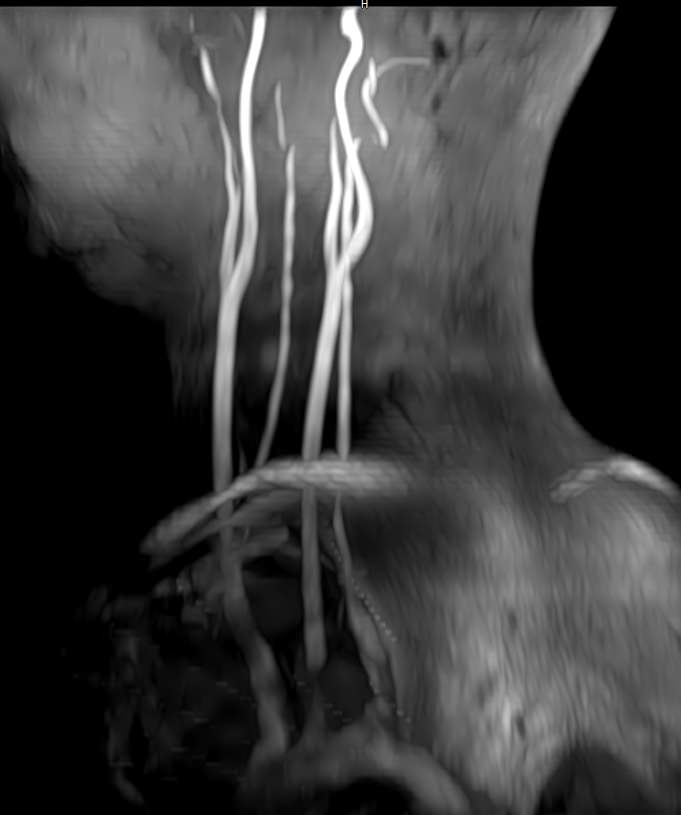

Шейный отдел позвоночника — это самый подвижный сегмент позвоночного столба, который испытывает повышенные нагрузки, подвержен травмам и развитию различных заболеваний. В эту анатомическую область входит 7 верхних позвонков, спинной мозг с отходящими от него нервными корешками, а также проходят крупные сосуды, кровоснабжающие головной мозг. К ним относятся плечеголовной ствол, сонные и позвоночные артерии.

Патологические изменения в сосудах шеи могут вызвать транзиторные ишемические атаки (преходящие нарушения мозгового кровообращения) и инсульты, которые являются частой причиной инвалидизации и смертельных исходов.

Наиболее частая причина патологии сосудов – атеросклероз, при котором в стенке артерии образуются холестериновые отложения в виде утолщения и впоследствии формируются бляшки. Атеросклеротические бляшки с течением времени сужают просвет сосудов, вплоть до полной окклюзии. Кроме того бляшки имеют склонность к изъязвлению и образованию тромбов. Реже встречаются воспалительные изменения сосудов (васкулиты). В некоторых случаях сдавление магистральных артерий шеи может происходить за счет патологии позвоночника, опухолевого процесса или травм.

Для того, чтобы оценить состояние шейных позвонков с прилегающими тканями и одновременно визуализировать крупные сосуды шеи, в нашей клинике выполняется комплексное обследование, включающее два протокола: МРТ шейного отдела позвоночника и МР-ангиографию шеи.

В клинике «Доступная медицина» комплексное обследование шейного отдела позвоночника одновременно с МР-ангиографией шеи проводится на новейшем высокопольном томографе экспертного уровня TOSHIBA VANTAGE TITAN 1,5 Тесла, который производит послойное сканирование исследуемой зоны в разных плоскостях, затем при помощи компьютерных программ преобразует полученные данные в трехмерные изображения шейного отдела позвоночника и кровеносной системы, что позволяет проводить точную диагностику и назначать пациенту своевременное лечение.

• участки сужения, извитость, образование петель и перегибов сосудов;

• ангиомы, сосудистые мальформации.